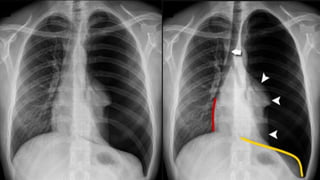

Tension

pneumothorax

Lung collapse

Mediastinal shift

Low flat

diaphragm

The side with pneumothorax is larger than the contralateral side.

Chest moves less during the respiratory cycle.

Tactile fremitus is absent.

The percussion note is hyperresonant.

The breath sounds are reduced or absent on the affected side.

The lower edge of the liver may be shifted inferiorly with a right-side

pneumothorax.

The trachea may be shifted toward the contralateral side if the

pneumothorax is large.